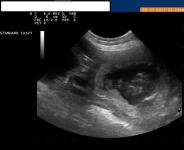

foto echo